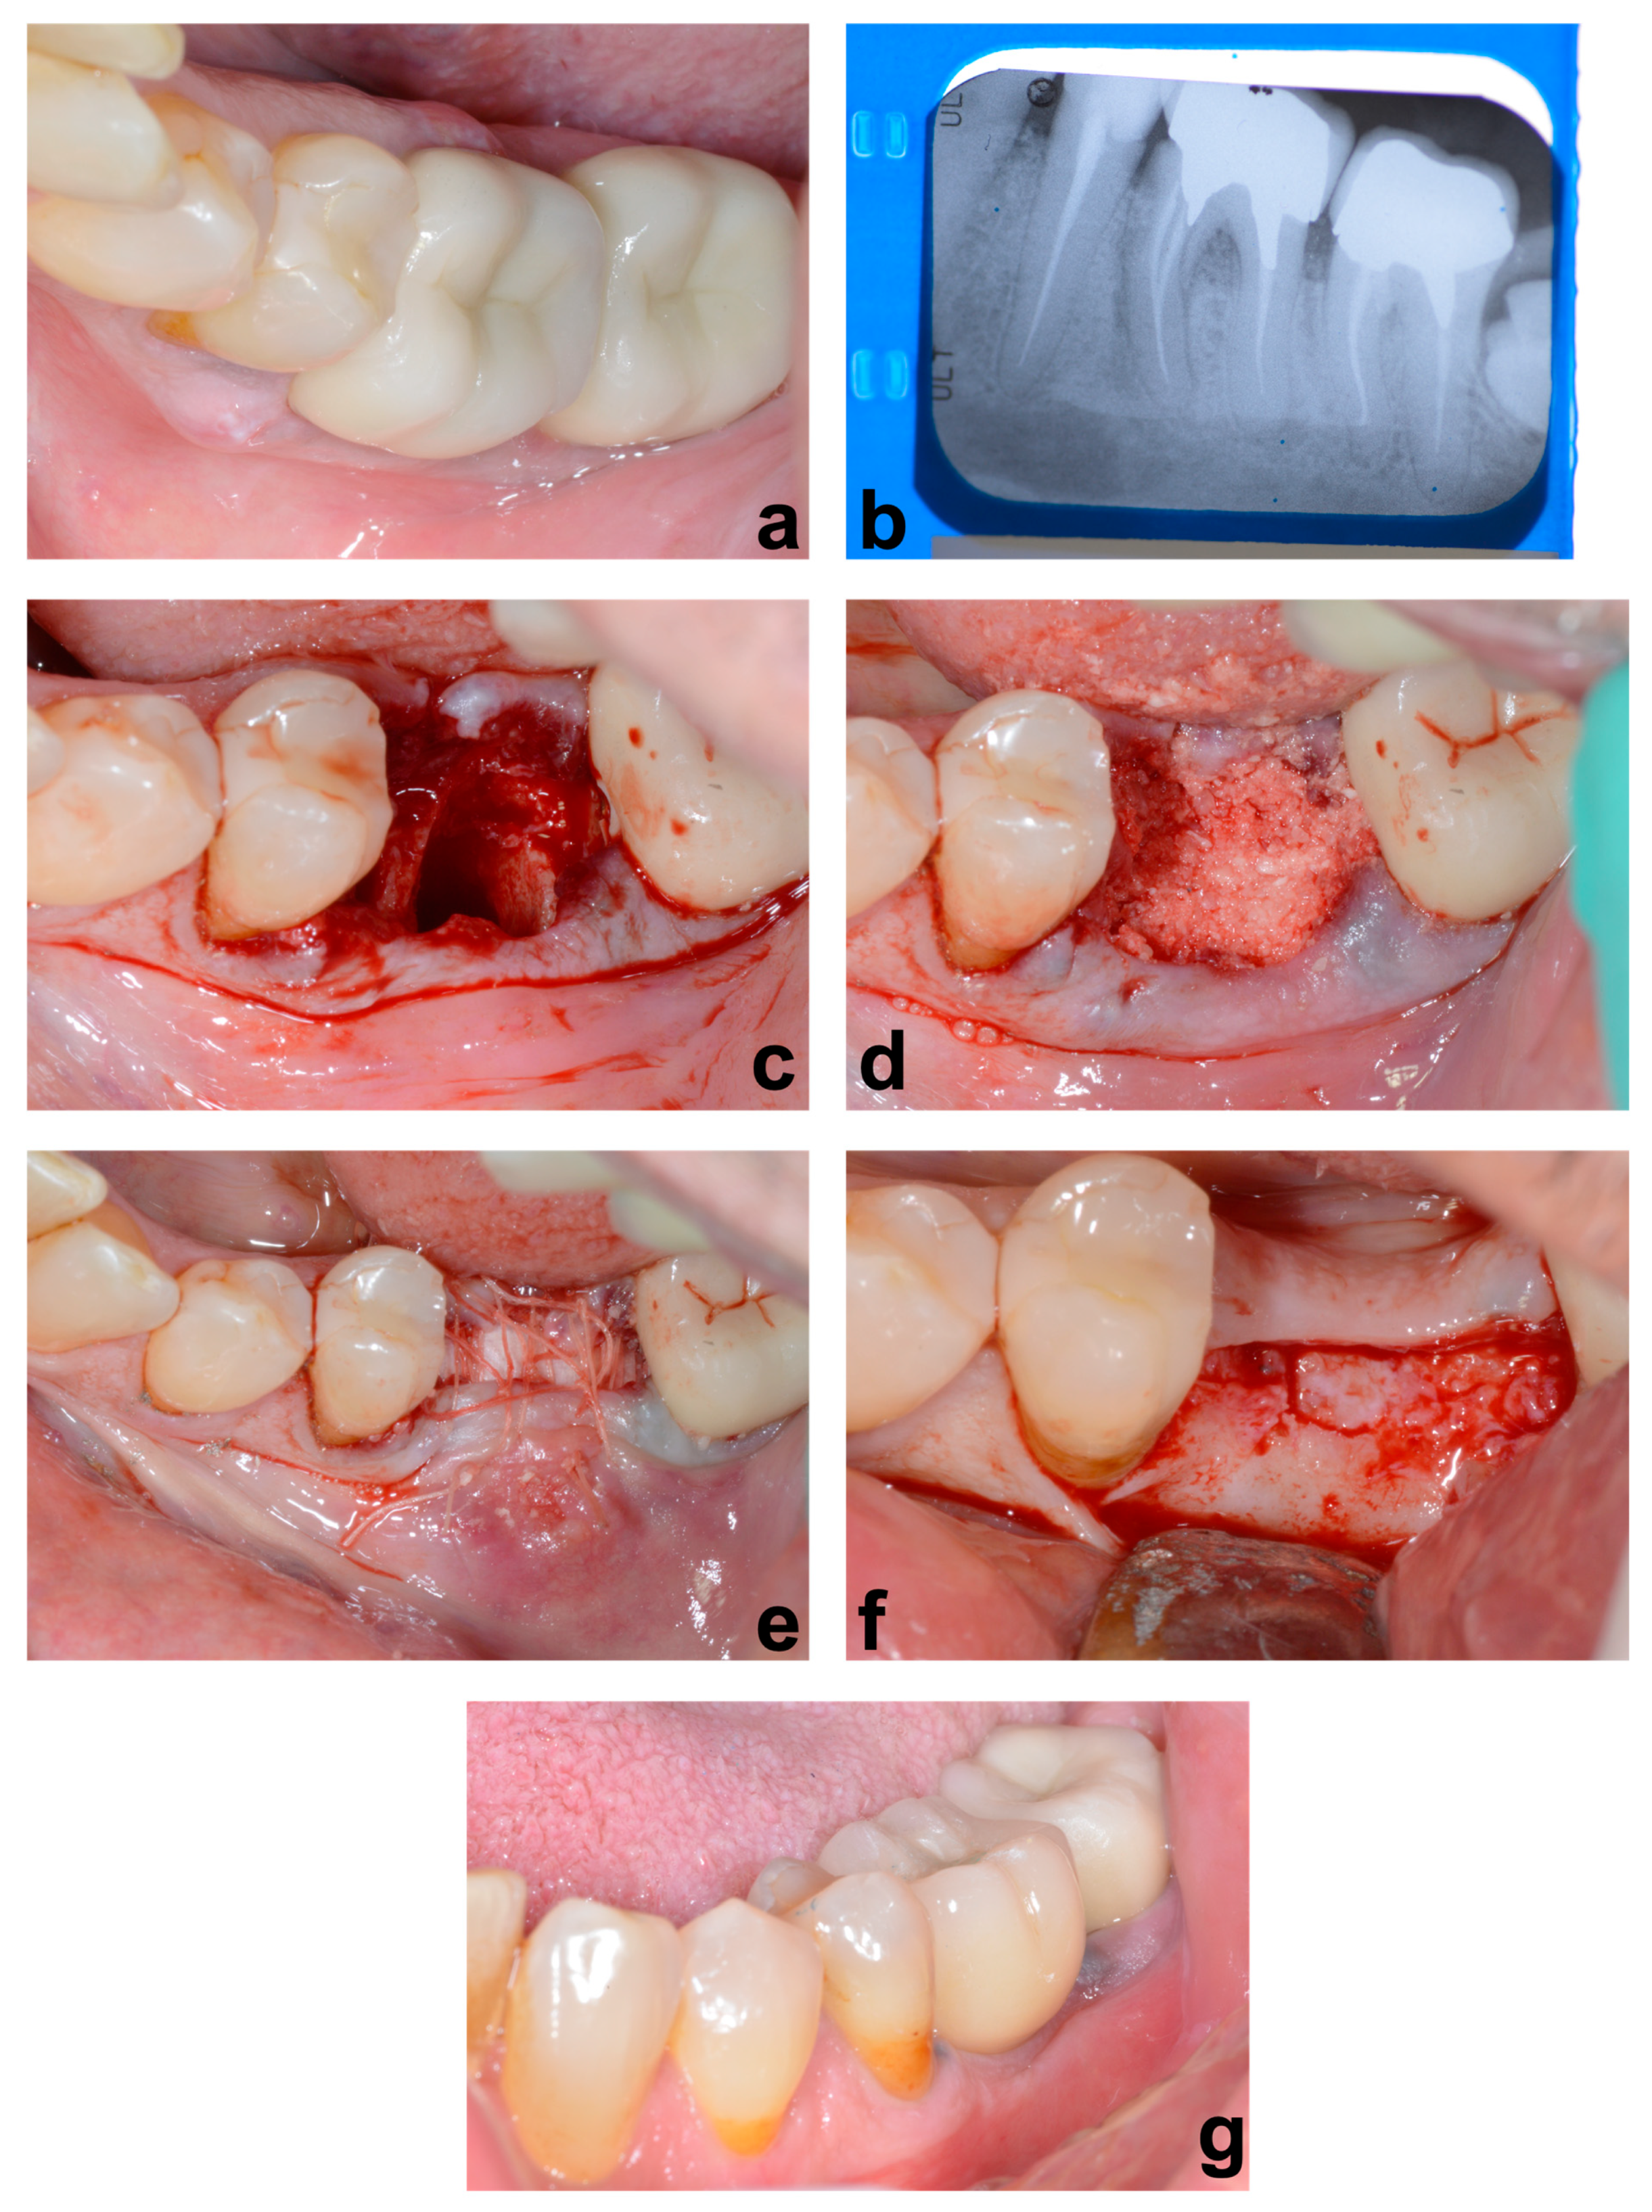

2. Materials and Methods

3. Results